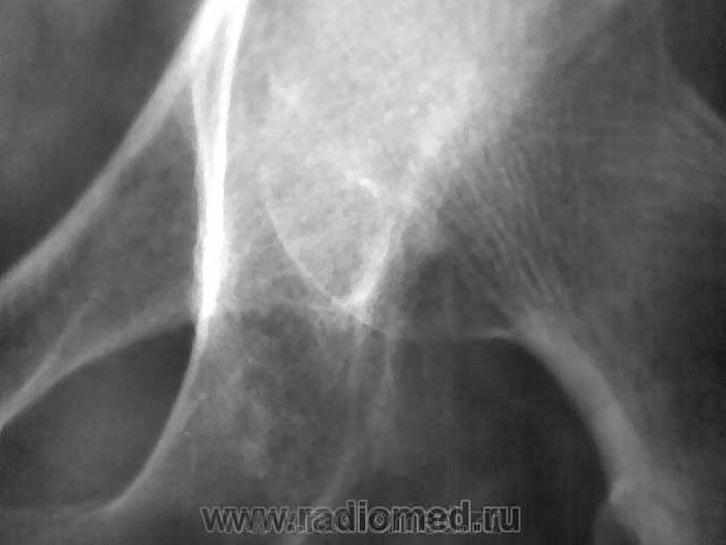

Не исключая остеолитический метастаз все же складывается мнение о суммации теней мягкотканного компонента, вот почему и было высказано мнение о пахово-мошоночной грыже.

Постараюсь отыскать снимок и пациента (исследование поводилось ещё осенью), если попытка будет удачной, можно в принципе и повторить R-грамму, но помниться, что кроме этой "капли", ни чего примечательного там не было.